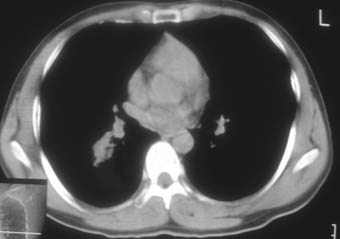

锁骨骨折复查,发现肺内高密度影,行ct检查。

男性,35岁,无任何感觉,无明显发热感冒病史。

纵隔窗!

右肺下叶背段斑片状阴影,边缘模糊,纵隔内未见肿大淋巴结,病人无发热及感冒史,要考虑浸润型肺结核,可结合ppd检查,或短期抗炎治疗复查。

右肺下叶背段长椭圆型病灶,边缘较规则,无明显分叶征、毛刺,远段未见阻塞征象,病灶较松散,纵隔窗明显小于肺窗,年龄35岁,支气管稍示变窄,纵隔内未见明显肿大淋巴结,这些都不支持肿瘤。病人无任何感觉,无明显发热感冒病史,首先考虑结核(也是结核好发部位),慢性炎症不能完全除外。